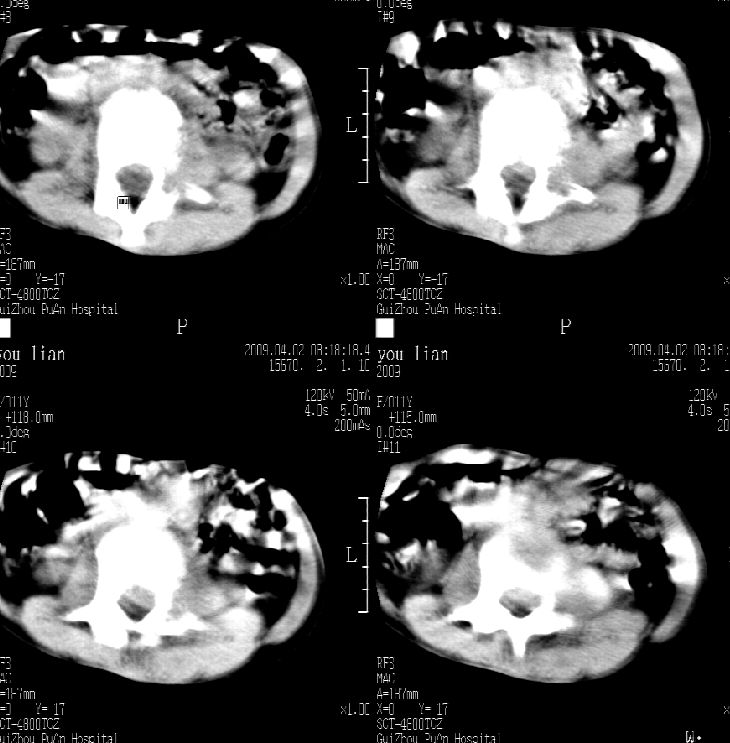

患儿女,11岁,因“腰痛,腰部活动受限10余天”入院。

10余天前,患儿无明诱因出现腰部疼痛,为持续性钝痛,以右侧为著,伴腰部活动受限,有发热,具体体温不详,无寒战、黄疸、盗汗、咳嗽,无尿频、尿急、肉眼血尿。

乍一看像是嗜酸性肉芽肿,但看到ct表现骨质破坏及软组织肿胀考虑结核可能性大,鉴别恶性肿瘤.

本例ct图像太不清楚了,而且不知道有没有传完,如果软组织病变只局限性于那几个层面的话多考虑嗜酸性肉芽肿,其次为其他肿瘤,结核椎旁软组织较广泛,在本例没有太典型表现,建议楼主(孩子父母吧)把所有的软组织窗图像(白色的那种)按顺序全部转上来.

考虑l3嗜酸性肉芽肿。